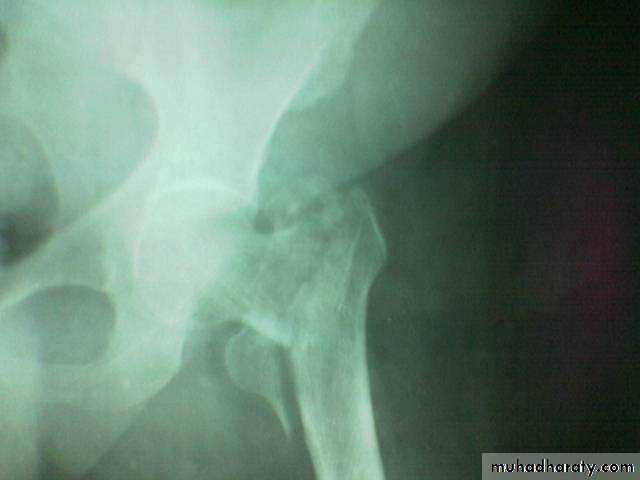

A vascular necrosis

By x ray appeared between 6weeks- 2 years.

It occur in 10% and raised to 40% if neglected more than 12 hours

Osteoarthritis ,a vascular necrosis or femoral head collapse may lead after several years to secondary osteoarthritis.